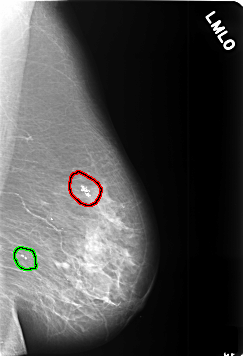

C_0391_1.LEFT_MLO

FILE: C_0391_1.LEFT_MLO.OVERLAY

TOTAL_ABNORMALITIES 2

ABNORMALITY 1

LESION_TYPE CALCIFICATION TYPE PLEOMORPHIC DISTRIBUTION CLUSTERED

ASSESSMENT 4

SUBTLETY 5

PATHOLOGY BENIGN

TOTAL_OUTLINES 1

BOUNDARY

ABNORMALITY 2